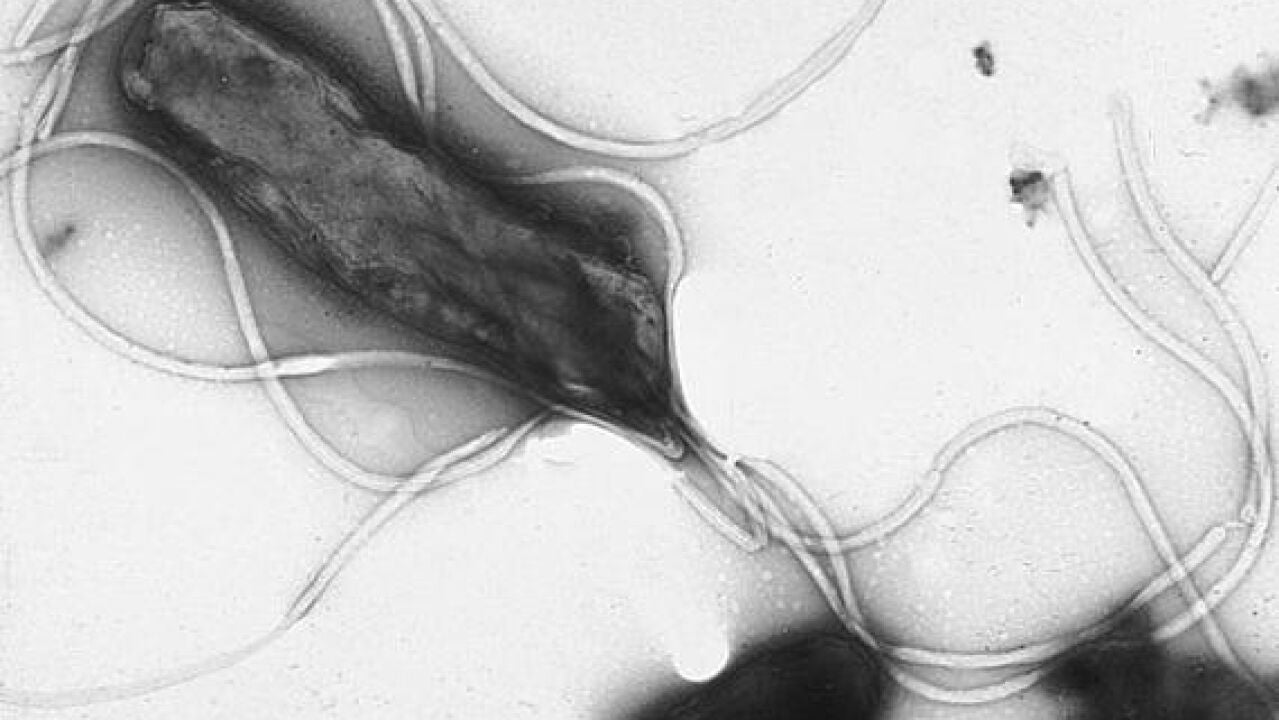

Un método de secuenciación genómica predice con exactitud la resistencia de 'Helicobacter pylori' a antibióticos